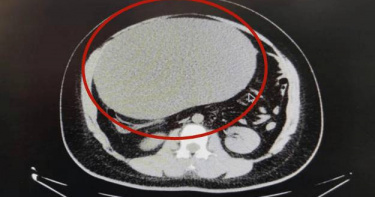

河南鄭州一名21歲的女生近日以為是增胖有成,腹部大得堪比懷孕,直到某日感到不適送醫,才知道腹部漲了巨大卵巢囊腫,重達8公斤,重量堪比懷了三胞胎!鄭州一名女生腹部長了巨大卵巢囊腫,重達8公斤。(圖/翻攝自民生頻道)綜合陸媒報導,這名女子近日上完廁所後,突然感到腹痛難忍,痛到幾乎不能走路,於是報警求助並送往醫院救治,到醫院後,醫生發現女子的腹部很大,宛如懷孕,而她自己卻以為是長胖,還自行服用了3個月的減肥藥。女患者囊腫的囊液取出來,也大概有5000毫升,相當驚人。(圖/翻攝自民生頻道)經CT檢查顯示,這名患者腹部有一個巨大的卵巢囊腫,手術切除後重達8公斤,相當於三胞胎的重量,比一個足球還大。醫師還透露,女患者囊腫的囊液取出來,也大概有5000毫升,相當驚人。這名女子經過治療後已恢復健康,醫生就提醒,一般發胖的情況是會在全身多部位體現,若只是局部出現異常膨隆的情況,建議要趕緊就醫檢查。